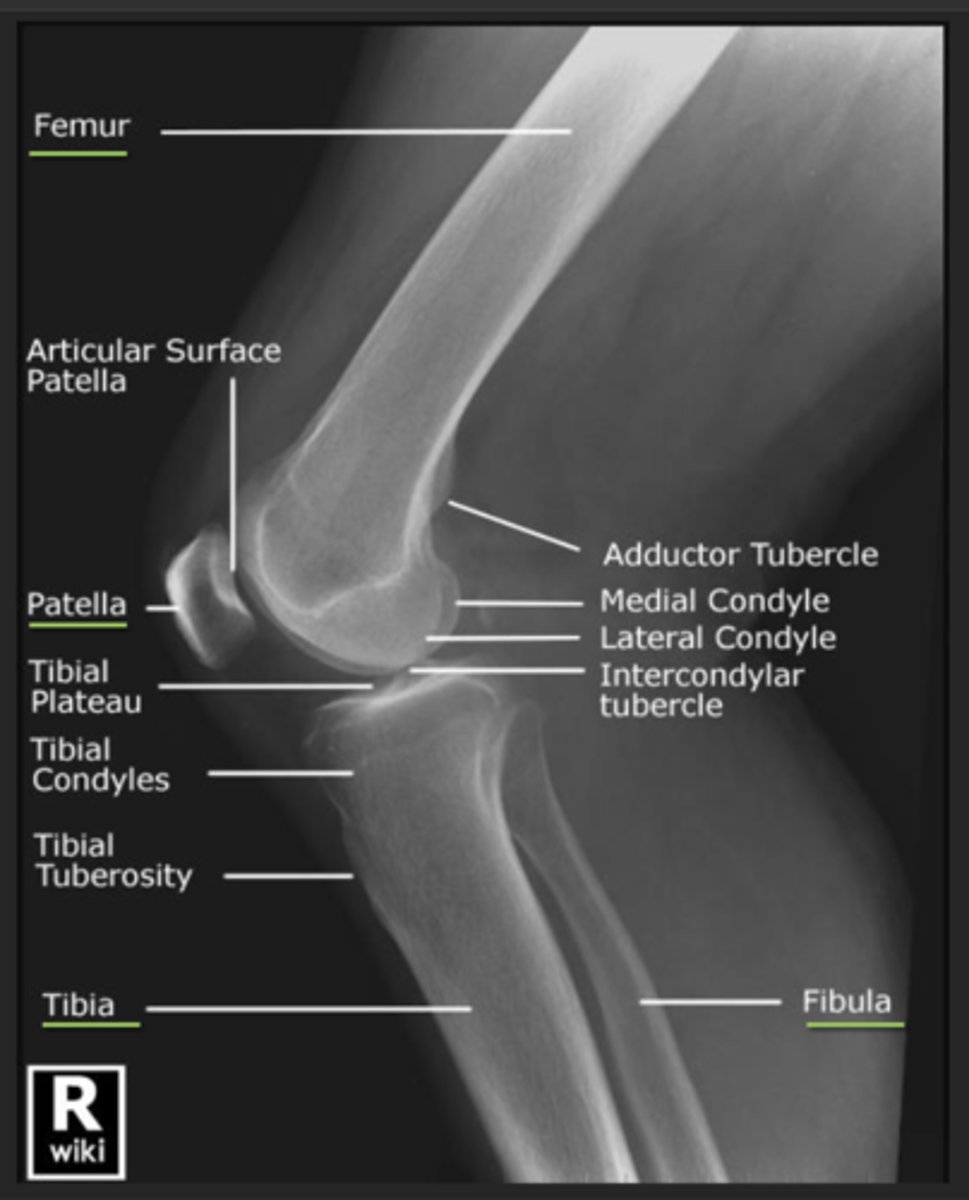

How should we COLLIMATE when doing a LATERAL KNEE projection? What structures should be included in the image?

- to include the knee joint, distal third of the femur, proximal third of the tibia and fibula and lateral soft tissue borders.

ALSO:

▪ The femoral condyles should be superimposed

▪ The patella should be clear of the femur

▪ Patellofemoral joint space demonstrated

▪ Approx 1/3rd of the head of fibula superimposed over the tibia